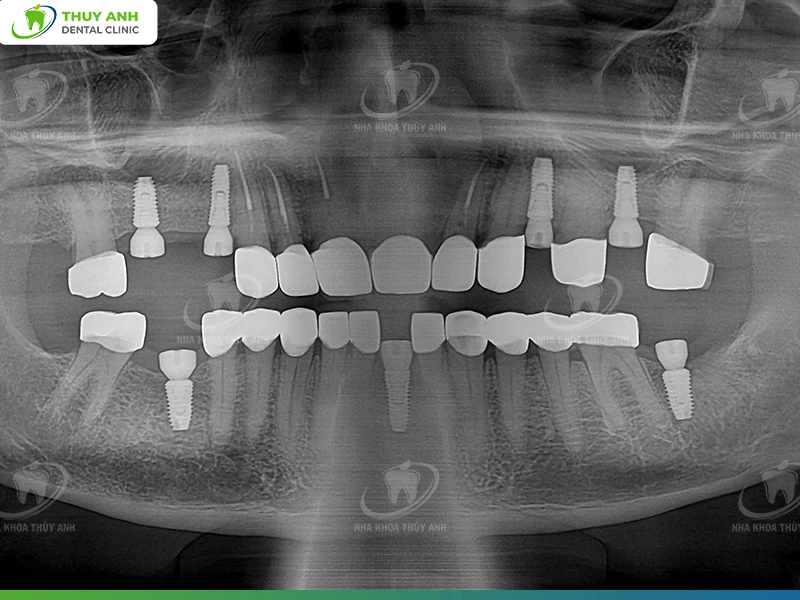

Final Treatment Plan

After thorough discussion, the final treatment plan included:

1. Endodontic treatment and restoration of upper anterior teeth

These teeth were severely worn and fractured. Root canal treatment and post placement help increase clinical crown height, supporting the restoration of vertical dimension.

2. Implant placement in missing areas

- 4 implants in the upper jaw

- 3 implants in the lower jaw

3. Full-mouth ceramic restorations

The goals are to:

- Restore tooth length

- Re-establish chewing function

- Improve smile aesthetics

Completion of Trip 1

After completing the implant surgery phase, Philip concluded his first treatment trip in Vietnam.

The initial results achieved:

- The occlusion was successfully re-established

- The new prosthetic system functioned effectively

- The implants were placed precisely according to the treatment plan